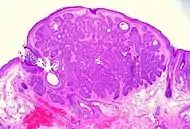

Characteristics

Basal-cell carcinoma cells appear similar to epidermal basal cells, and are usually well differentiated.[15]

In uncertain cases, immunohistochemistry using BerEP4 can be used, having a high sensitivity and specificity in detecting only BCC cells.[16]

Nodular basal-cell carcinoma (also known as "classic basal-cell carcinoma") accounts for between 50% and 80% of all BCC.[2] It most commonly occurs on the sun-exposed areas of the head and neck.[2] Histopathology shows aggregates of basaloid cells with well-defined borders, showing a peripheral palisading of cells and one or more typical clefts.[17] Such clefts are caused by shrinkage of mucin during tissue fixation and staining.[18] Central necrosis with eosinophilic, granular features may be also present, as well as mucin. The heavy aggregates of mucin determine a cystic structure. Calcification may be also present, especially in long-standing lesions.[17] Mitotic activity is usually not so evident, but a high mitotic rate may be present in more aggressive lesions.[17] Adenoidal BCC can be classified as a variant of NBCC, characterized by basaloid cells with a reticulated configuration extending into the dermis.[17]